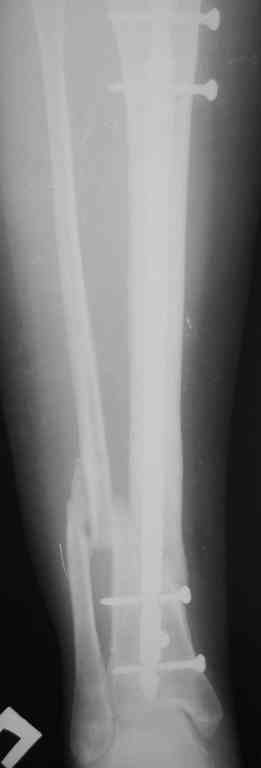

Re: Ложный сустав голени перелом штифта

Прилагаются.

Да , обсуждалась и оптимальным штифтом был выбран " Мастер" Остеомед 10 мм и винты 5 мм, но увы все наши благие намерения разбились о нашу действительность и материальные возможности больной, обращение ее в страховую компанию и т.д., вообщем выкручивались из внутренних резервов, а они были такими 9 мм штифт Остеомед, под 4 мм винты. Ограничили нагрузку. Ошиблись еще и с оценкой сращения, дали полную нагрузку+ больная поправилась на 18 кг, и вот теперь имеем , что имеем.

Действитльность и возвожности остались прежнее, во внутренних резервах есть 11 мм стержень универсальный ( реконструктивный) "Деост-CHM" много спиц и аппарат + ось конечности и отломок штифта и надежда на Ваши советы.

С длиной все в порядке, ось ушла, под ЭОП посмотрели ось, коррегируется руками, от аппарата больная категорически отказывается, уже носила до штифтования. Планируем одномоментное рассверливание и перештифтования, наложим спицевой дистрактор. По поводу удаления обломка есть идея, отдали чертежик на изготовления, если получится то удалим без окончатой остеотомии.

От пластики в зоне перелома останавливает возможность дремлющей инфекции и рубцовый процесс., остановились только на рассверливании. По результатам скину на форум информацию.